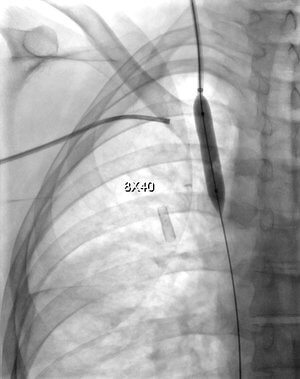

28 year old female patient with CKD requiring dialysis through a right upper extremity AV fistula. She presents with right upper extremity swelling.

Comment: This chronic occlusion was recanalized using the PowerWire RF Guidewire (Baylis Medical). Access was gained from the internal jugular vein as well as the common femoral vein in order to the potential for relatively straight line passage of the PowerWire. Once access was achieved via all of these veins, a snare was positioned in the SVC and the PowerWire was introduced via the right internal jugular vein. Passage of the wire was found to be extravascular in this case, so covered stents were used to cover the area of occlusion in the proximal subclavian vein extending into the brachiocephalic vein and the upper SVC.